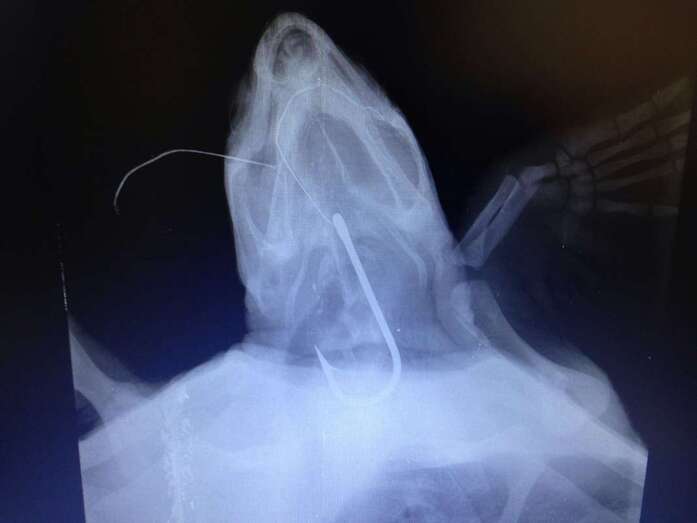

Otro de los retos a los que se ha enfrentado el equipo de veterinarios del Centro de Recuperación de Fauna Silvestre de Tafira durante 2016 es la operación que salvó la vida a una gran tortuga marina encontrada en la playa de Vargas, en el municipio de Agüimes. El animal llevaba mucho tiempo con un anzuelo de grandes dimensiones alojado en la garganta.